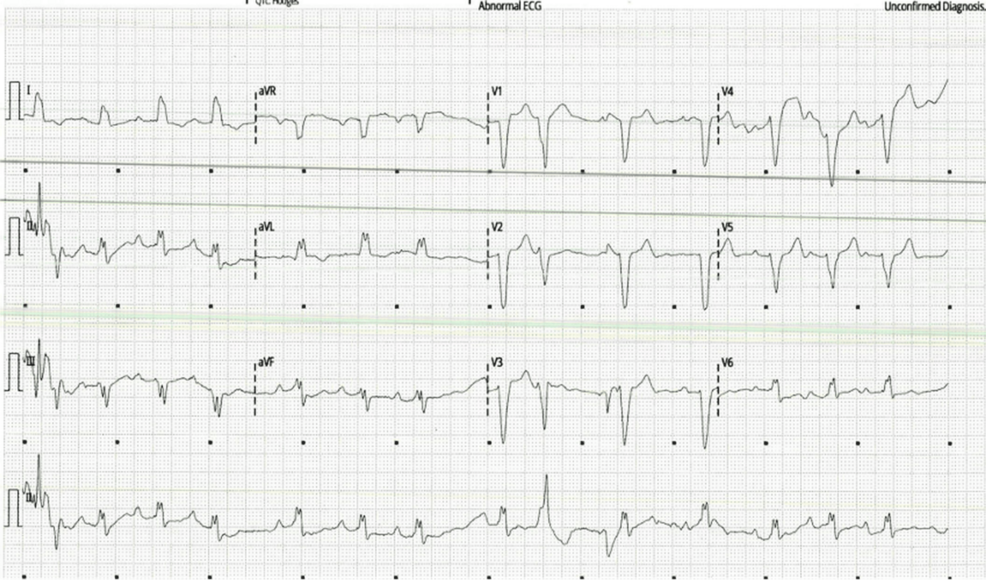

Across nearly all specialties, technology is no longer a supplement but an integral component of practice. Artificial intelligence (AI) and machine learning are poised to revolutionize diagnostics, treatment planning, and even surgical procedures. For example, in Radiology, AI algorithms are already assisting in the detection of subtle anomalies in medical images, improving accuracy and reducing radiologist workload. Similarly, Cardiology is benefiting from AI-powered ECG analysis and predictive modeling for heart failure.